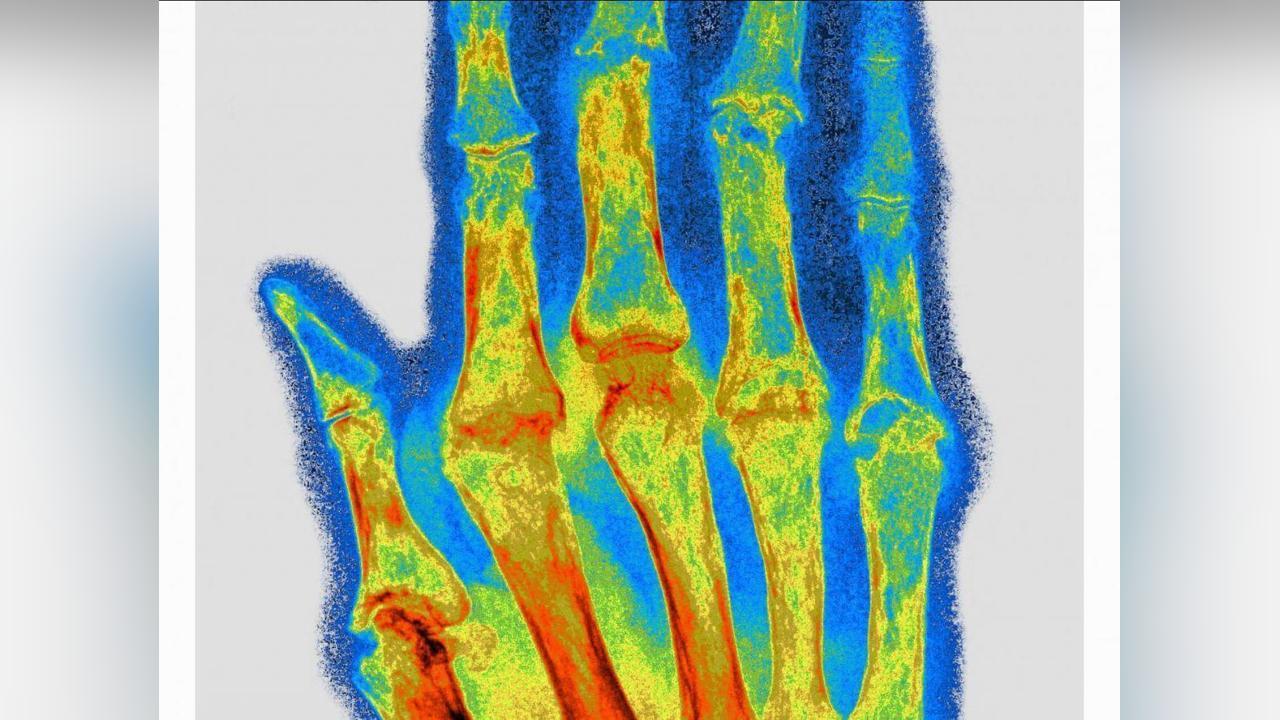

Exemple ici avec la polyarthrite rhumatoïde, une maladie inflammatoire auto-immune chronique entraînant douleur, gonflement et, à terme, une destruction articulaire caractérisée par une inflammation synoviale persistante. Cette dernière conduit à une érosion osseuse et à une déformation articulaire.